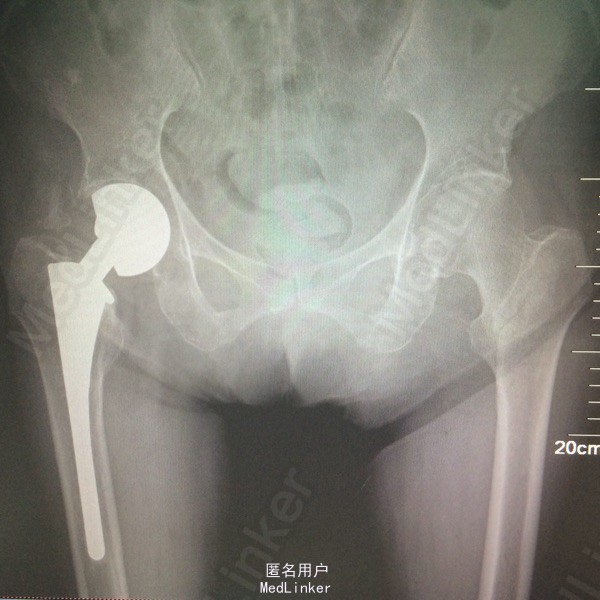

左股骨转子间骨折

89岁女性,因跌倒致左髋部疼痛伴活动受限3小时收入院 既住1年前因右股骨颈骨折行右人工股骨双动头置换术 有高血压病史多年,血压控制可

左下肢轻度外旋,左髋部压痛及左下肢轴向叩击痛(+),左髋关节活动受限 胸片提示右上肺炎 心脏彩超提示左房大,舒张功能减退,EF58% 髋关节X光提示左股骨转子间骨折

1、左股骨转子间骨折 2、右肺炎 3、高血压病 4、右人工股骨头置换术后 行左股骨转子间骨折闭合牵引复位PFNA内固定术

术后两天下地部分负重行走,1周出院,恢复良好